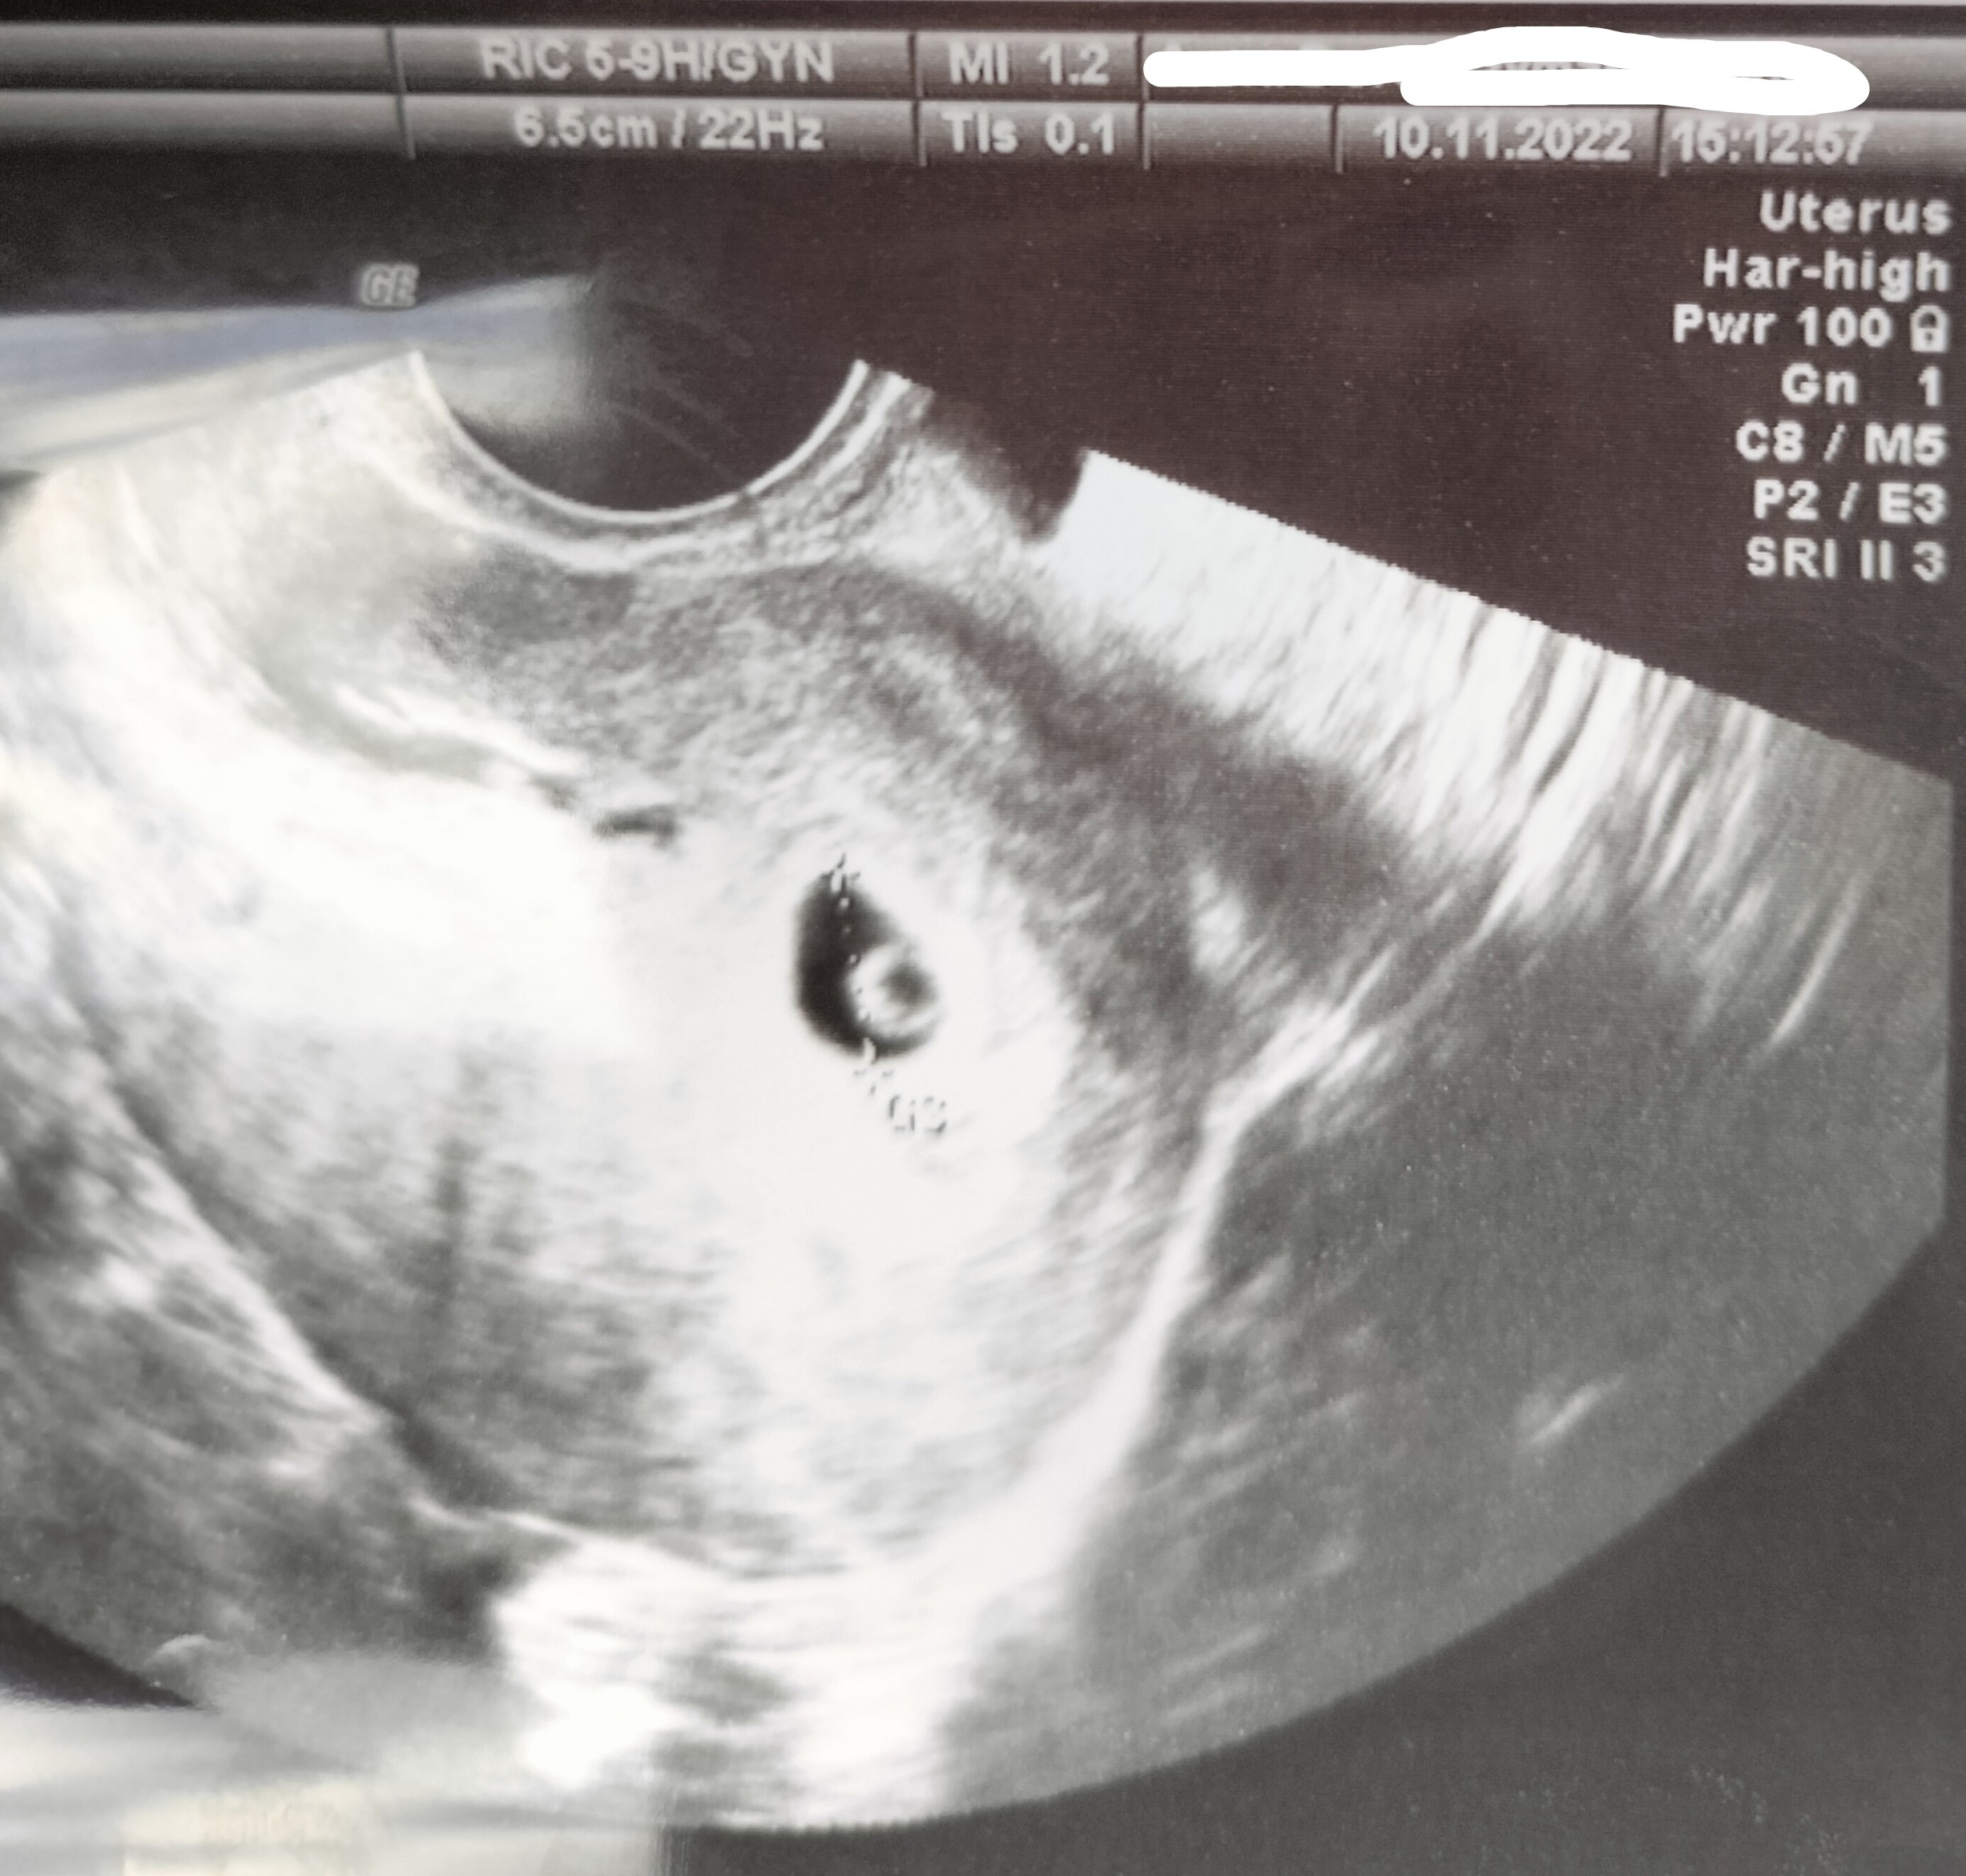

Ja mam pęcherzyk ciążowy z pęcherzykiem zoltkowymMamy podobne

lekarz mówił ze to bardzo wcześnie i może nie być widoczny także pewnie jest dobrze u CiebieJa mam pęcherzyk ciążowy z pęcherzykiem zoltkowymi od dzisiaj zanik objawow i schize, uspokaja mnie trochę zdjęcie z USG. Ale dzidziusia jeszcze nie było

który tydzień bo chyba się gdzieś zakręciłam i nie pamietam ?Ja mam pęcherzyk ciążowy z pęcherzykiem zoltkowymi od dzisiaj zanik objawow i schize, uspokaja mnie trochę zdjęcie z USG. Ale dzidziusia jeszcze nie było

6t2 d a USG z równego 5 tcktóry tydzień bo chyba się gdzieś zakręciłam i nie pamietam ?